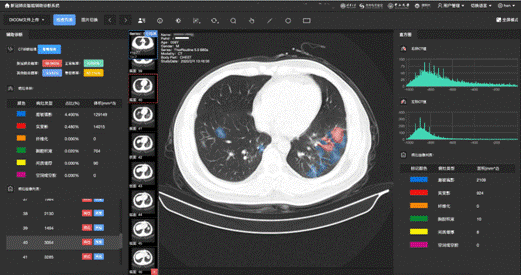

此外,通过医生手工标注的四千余张CT影像的典型病灶,系统可以对新冠肺炎、其他病毒性肺炎及细菌性肺炎的五类典型病灶(磨玻璃影、实变、空腔空洞等)自动进行精准定位,通过精准分析每一个病灶的大小和变化,可以作为药物筛选检测临床试验的判别标准。

基于国际上肺部病变及肝损伤相关研究结果及临床指标,研究团队制定了综合评分系统(c-score),该系统可以对新冠肺炎的危重症进行预测,为临床提供更为准确的预测模型和生存曲线分析,从而便于一线医务人员及时介入治疗并适当地分配资源。此项研究不仅代表了技术上的突破性进展,更为临床医生诊断决策和病情进展、预后管理提供了有效依据,目前已经在中山大学孙逸仙纪念医院、武汉金银潭医院、湖北宜昌医院等进行了部署应用,并通过国家生物信息中心进行线上推广。希望随着成果的公布,可以为国际新冠肺炎疫情防控作出贡献。

新冠肺炎影像辅助诊断应用界面